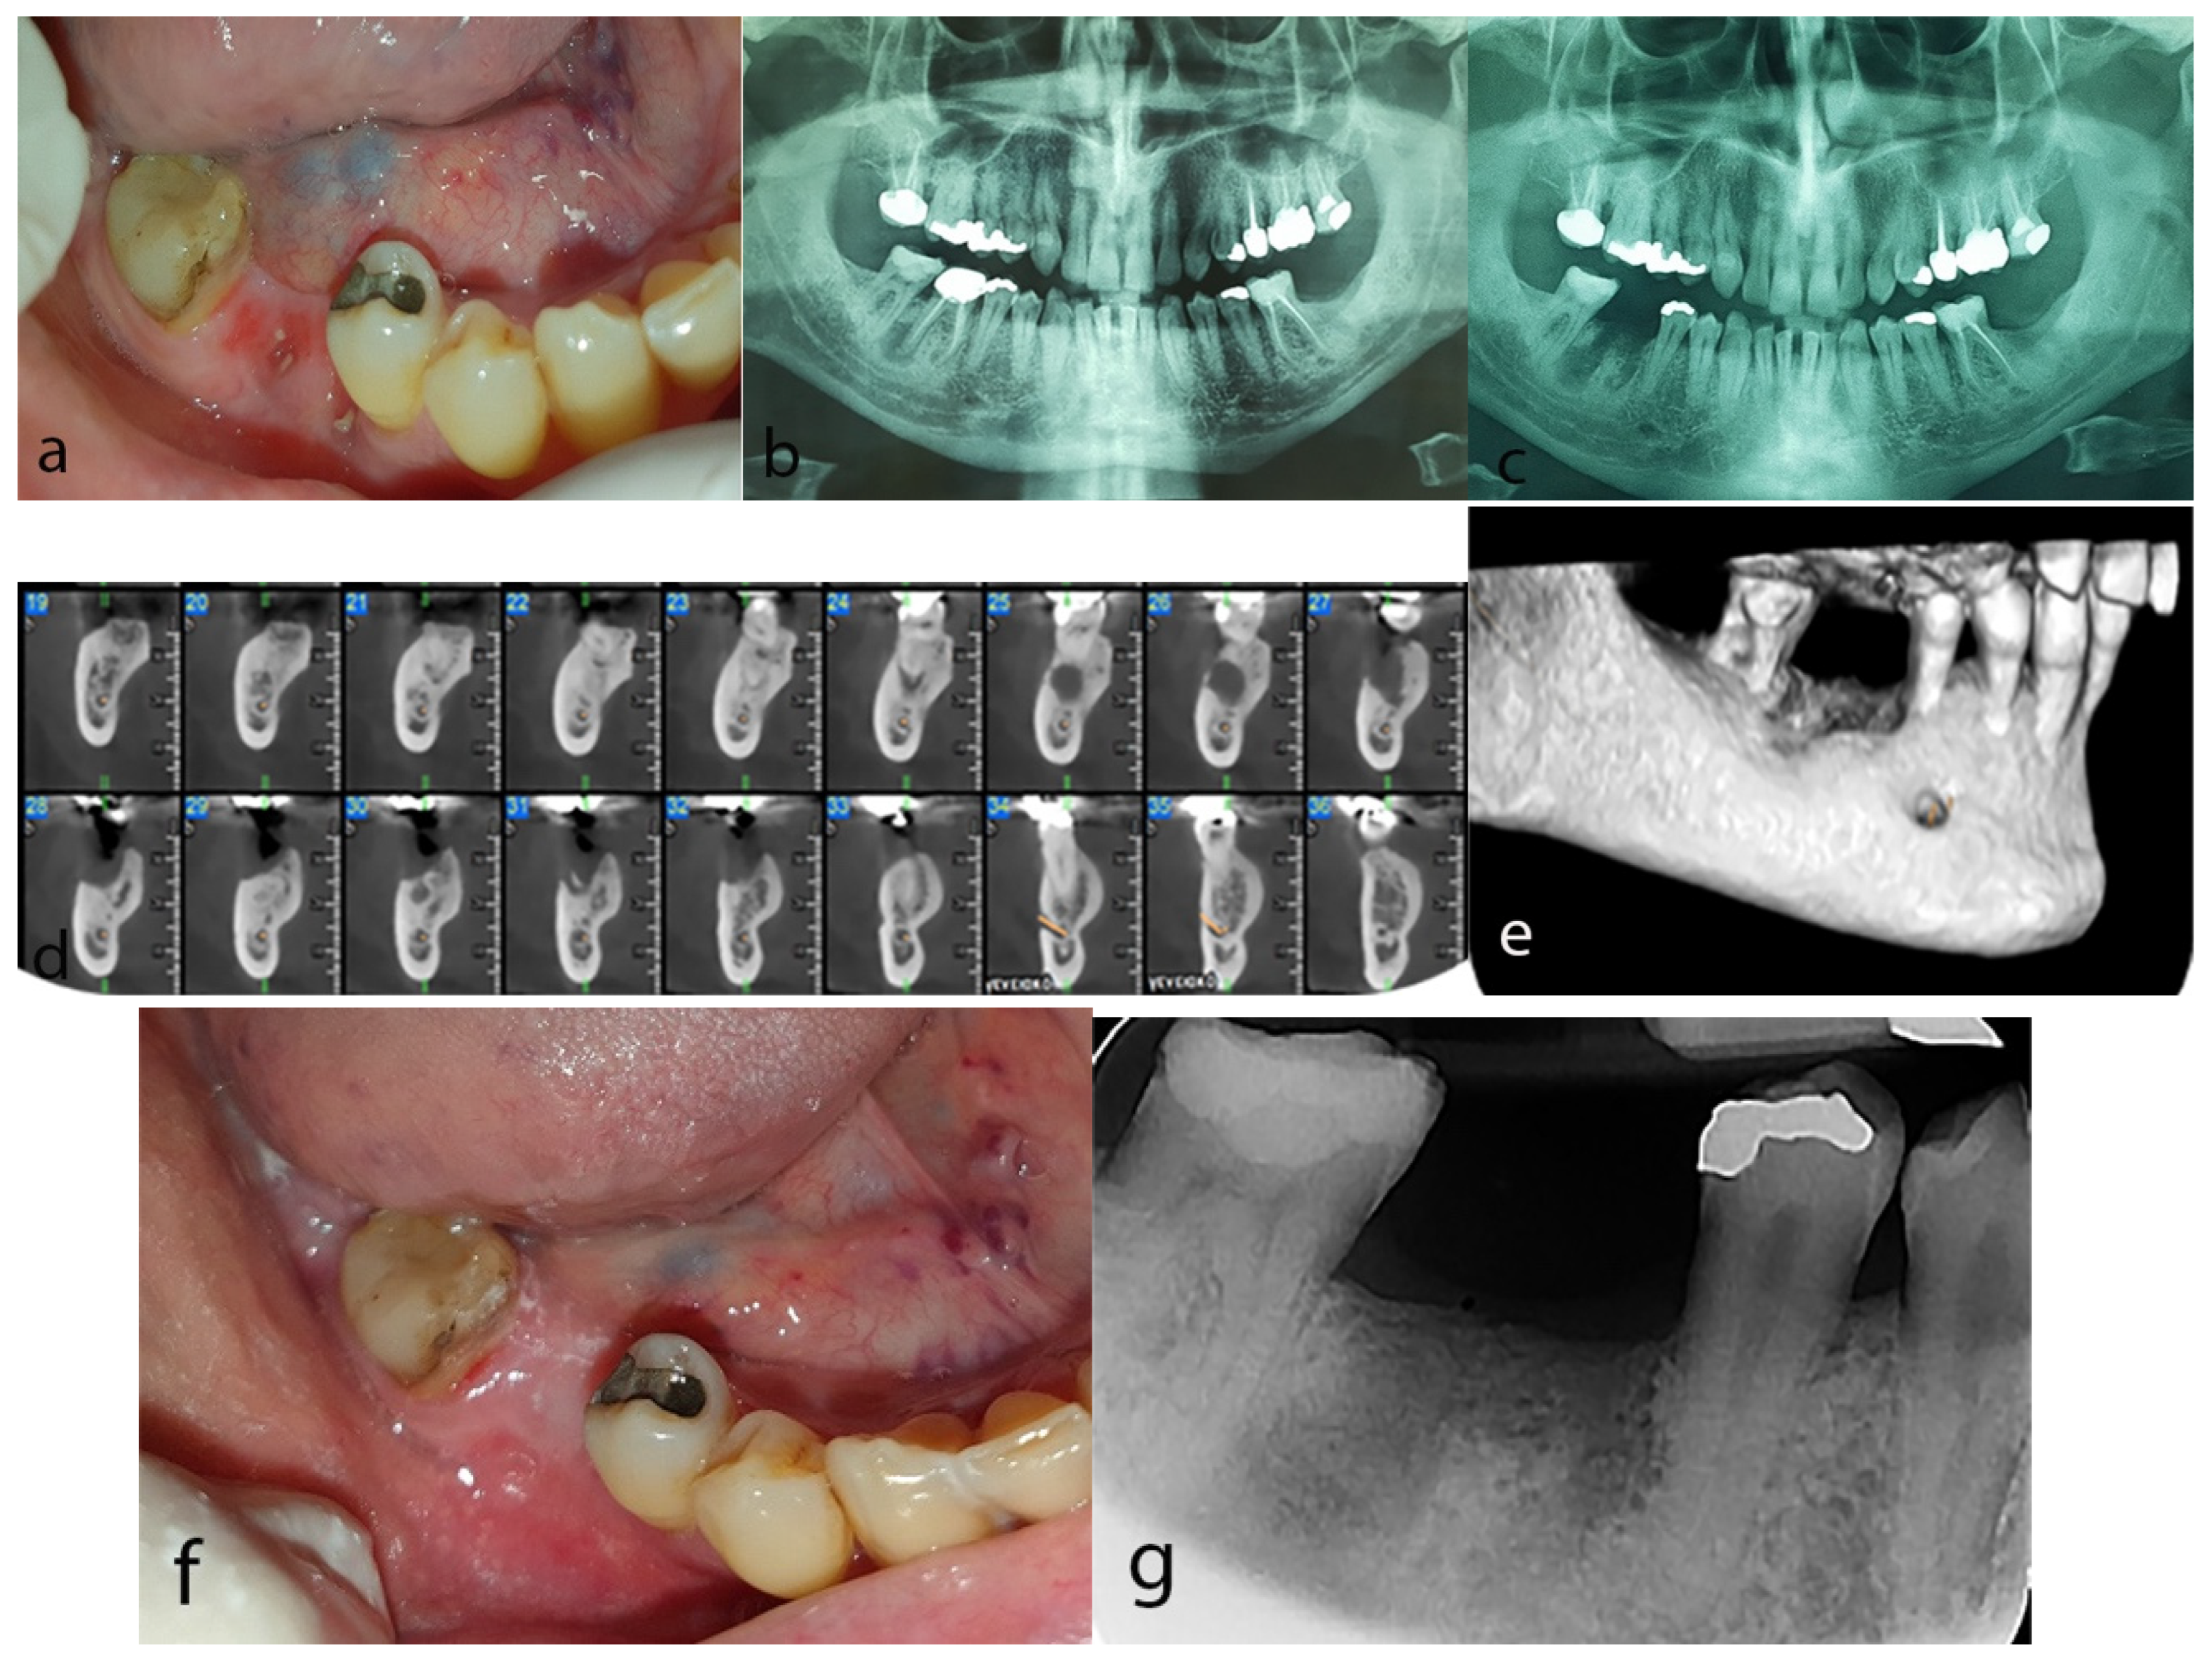

2.2. Case 2

2.3. Case 3